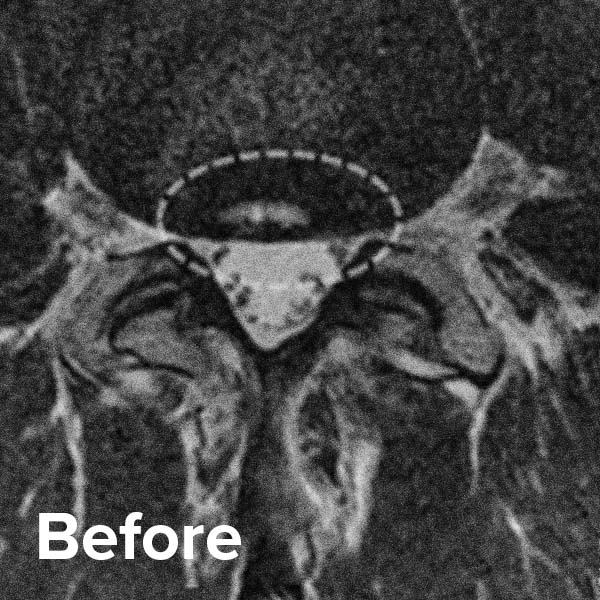

Annular Tear or Fissure eHealthStar Disc Tear Meaning A spinal disc tear, also known as an annular disc tear, is a crack or rupture in the outer fibrous ring (annulus fibrosus) of one of the. Back pain is the number one reason to see. What is a herniated disk? A herniated disk is an injury of the spine (backbone). A herniated disk occurs when some of the nucleus. Disc Tear Meaning.